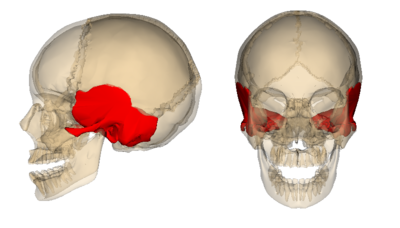

“A hipótese é de que o disco atingiu e causou uma fratura na região do osso temporal, causando uma lesão na artéria carótida, um vaso importante do sistema cardiovascular, que envia sangue do coração para o cérebro fornecendo oxigênio e nutrientes. Para melhor localização, sabe aquela artéria que ao colocar o dedo no pescoço pode sentir a pulsação? Exatamente esta. Veja como ela é superficial e isso coloca em risco uma pancada nesta região causando lesões neste vaso sanguíneo”, explica.

Além disso, Abreu lembra que o impacto pode ter causado lesões que limitou o suprimento de sangue para o cérebro causando a hemorragia cerebral. “Quando acumulado muito sangue no cérebro há uma herniação cerebral, aumento da pressão intracraniana desligando diferentes áreas importantes do cérebro entre elas o controle da respiração. O próprio osso pode danificar a região ao estilhaçar”.

O neurocientista lamenta que tudo isso se resume a uma grande fatalidade para o jovem atleta russo: “Ele teve azar, já que o disco atingiu uma das poucas regiões vulneráveis no capacete de hóquei, na região da orelha. Isso serve de alerta para que construa capacetes que também possam cobrir essa região para evitar este tipo de tragédia”, completa.